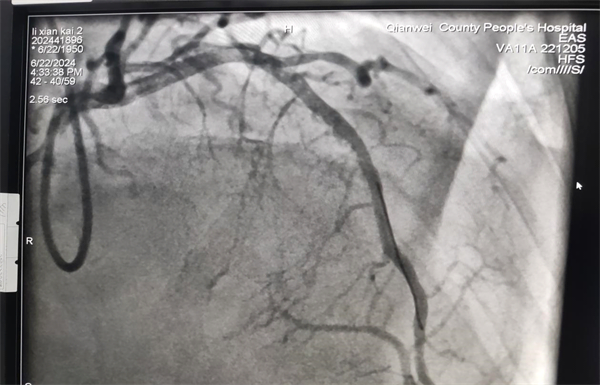

检查后需及时处理,彭宇立即为患者行支架植入治疗,根据血管内超声结果,选择合适大小及合适长度的支架精准植入,术后血管内超声清楚显示血管通畅,植入支架直径与血管直径完全匹配,贴壁情况良好,无夹层及血肿,手术顺利。目前患者胸闷、胸痛症状缓解,恢复较好,择日出院。

PCI术后造影